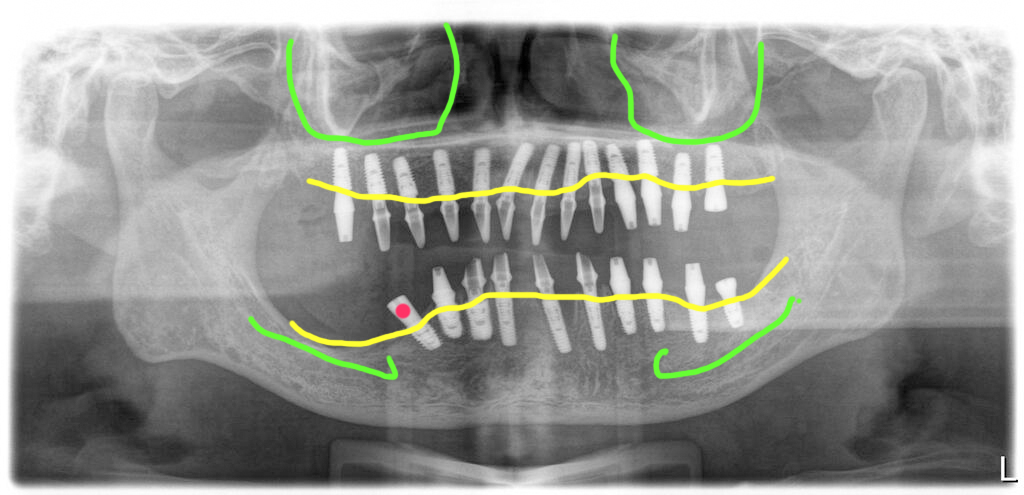

상악에는 13개, 하악에는 10개 식립, 신경근처는 기울여서

수술직후의 파노라마 사진입니다. 상악에는 13개의 임플란트를, 하악에는 10개의 임플란트를 식립했지만 신경과 너무 가까운 부위는 피해서 심었습니다.

그래서 신경 근처의 임플란트는 뒤쪽으로 일부러 기울여서 식립을 해서 이후 보철을 만들 때 조금이라도 뒤쪽을 서포트할 수 있도록 했습니다.

심지 않은 부분에는 캔틸레버로 치아를 하나 연결할 계획이므로 기울여서 식립하는 것이 보철을 할 때 조금은 유리할 수 있습니다. 하지만 아무래도 이 부분은 다른 부분에 비해 취약할 수 있으므로 좀 더 섬세한 관리가 필요하게 됩니다.